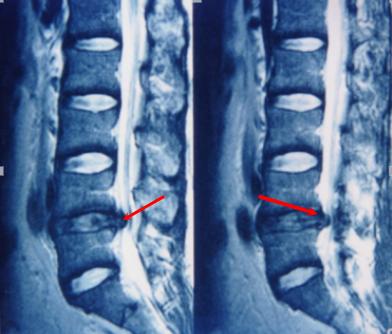

脊髓造影:往脊髓腔里面打造影剂后拍个片子,准确率可以达到80%,但无法良好的显示神经根,同时有创,一般很少用。

磁共振检查:跟CT一样,具有确诊价值,同时由于其成像原理,对于观察神经以及是否存在神经压迫水肿信号,有独特的优势,也是目前诊断腰椎间盘突出,明确神经压迫的主要检查,老百姓没学过医的也可以看得到的“突出”!